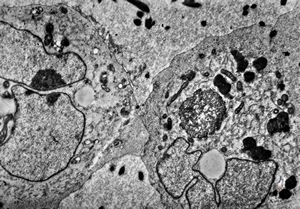

M,62y. | bone marrow - plasmocytoma

M,64y. | bone marrow - plasmocytoma